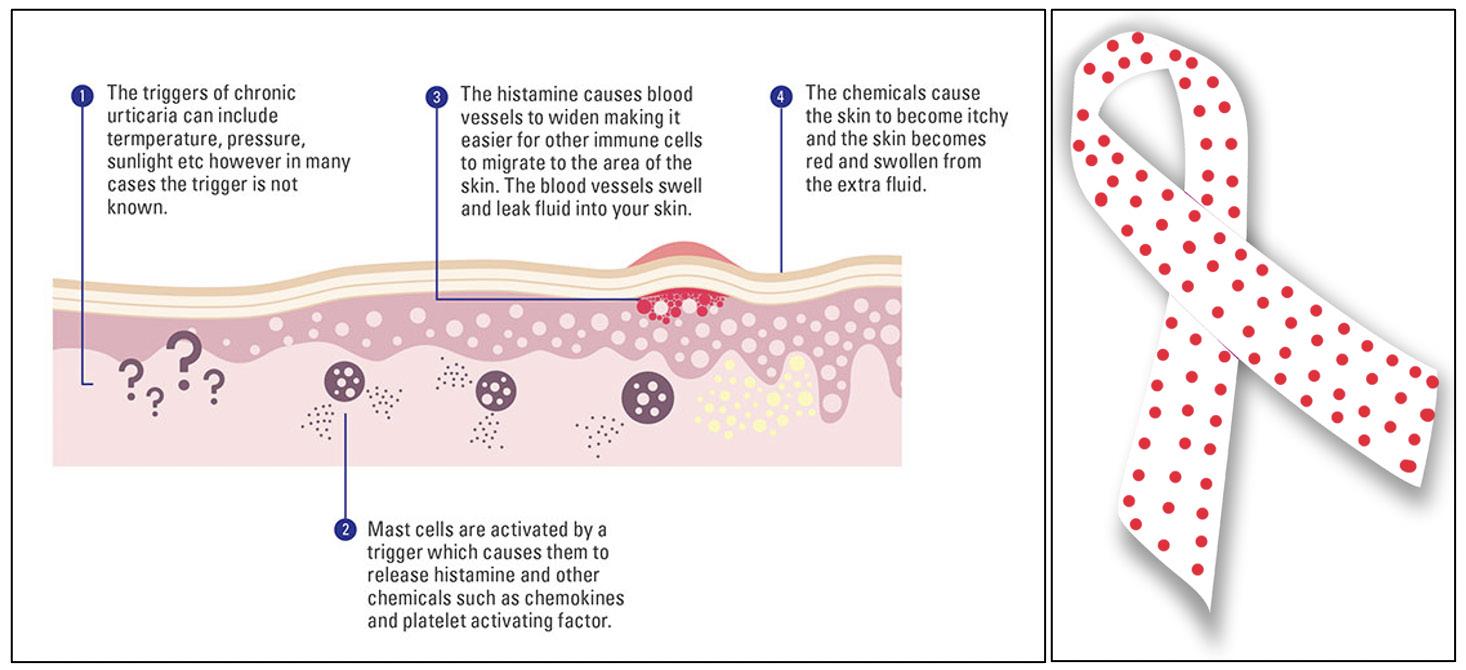

Image 2: An image of the machine that can execute the external beam radiation therapy. is machine uses beams from three types of particles: photons, protons, and electrons (Baskar et al., 2012; National Cancer Institute, n.d.). Photon beams “do not stop” until they reach the cancerous tumor, travelling through normal tissue as well. Proton particles can also reach the deep tumors, but they “do not scatter radiation” as the photon beams do (National Cancer Institute, n.d.). However, there is a higher price for these machines, making the use of these very limited. Electron particles cannot travel as deep as the photon and proton beams and are mainly used for surface tumors (Schulz-Ertner et al., 2006; Washington & Leaver, 2015; National Cancer Institute, n.d.). Image Source: Flickr to long-term problems, such as a secondary cancer, which is a cancer that has either originated from the rst kind and has mediatized to another location of the body, or a secondary type of cancer that was caused from the treatments of the rst (which is more common with radiation therapy). Extreme amounts of radiation can even lead to death. e quantity of radiation can be determined by the concentration of radiation photons and the energy of the individual photons. If one area of a body has received the limit of radiation, another part of the body can only be treated with radiation therapy if it is far enough from the previous area (Sadeghi et al., 2010; National Cancer Institute, n.d.).